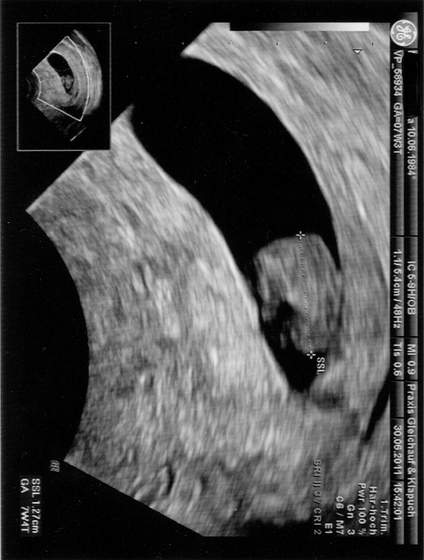

Mamuska - gratuluję ślicznego bąbelka oraz zobaczenia serduszka. Ja serduszko też widziałam, ale nie dał mi zdjęcia usgie do domu

dostanę dopiero 11.07